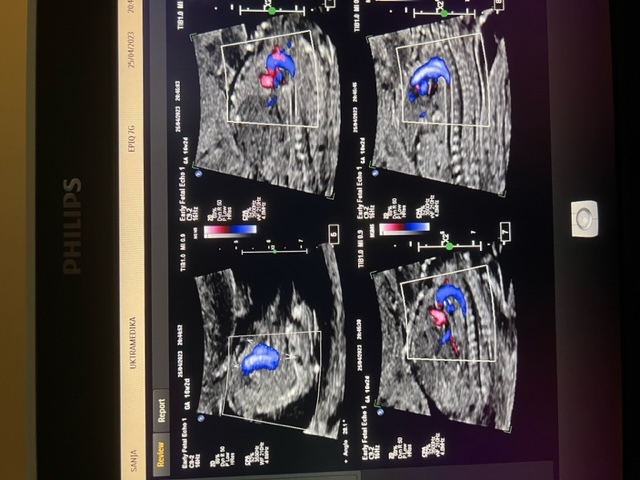

A. Dmitrović, K. Jeremić, U. M. Babić, M.Perović, T. Mihailovic, D. Oprić, N. Zečević, M. Gojnić- Dugalić: "Early fetal heart ultrasonography as additional indicator for chromosomopathies" (CEOG) u časopisu "Clinical and Experimental Obstetrics & Gynecology". Simpozijum "Radjanje ili odumiranje Srbije", Udruženje za perinatalnu medicinu Srbije, Beograd. "Modern hernia surgery of antero-lateral abdominal wall - open or laparoscopic approach", Serbian Hernia Society, Health Center Arandjelovac. "Ultrazvučna dijagnostika gastrointestinalnog trakta", Kongres privatne lekarske prakse, Beograd "Gastroenterologija danas, prevencija, dijagnostika, terapija", Kongres privatne lekarske prakse, Beograd. "Kardiologija- antikoagulantna i antiagregaciona terapija", Kongres privatne lekarske prakse, Beograd. "Mentalno zdravlje zena", Kongres privatne lekarske prakse, Beograd. "Hypertenzija - savremeni terapijski pristup", Kongres privatne lekarske prakse, Beograd. Doc. Tihomir M. Mihailović: "Ultrazvučna dijagnostika gastrointestinalnog trakta" na simpozijumu “Gastroenterologija danas, prevencija, dijagnostika i terapija", Kongres privatne lekarske prakse, Beograd.

Histerosalpingo-sonografija (HSSG)- Hy-Co - Sy, i kontrastna histero-sonografija Hy-Co Skraćen grlić materice Virusna infekcija u I trimestru trudnoće: Ultrazvučna dijagnostika i lečenje Frontomaksilarni ugao - Značaj i primenjivost novog ultrazvučnog markera u I trimestru trudnoće Fetalna ehokardiografija za vreme provere prozračne zone vrata Očinstvo nakon operacije varikokele - Preoperativna ultrazvučna procena uspeha operacije Frontomaksilarni ugao Paraovarijalne / paratubarne ciste Ultrazvučna dijagnostika Down-ovog sindroma u trudnoći DOWN – sindrom. Ultrazvučni skrining baziran, na osobini lica i dužini prsta u ranom II trimestru Stepen otkrivanja ranom fetalnom ehokariografijom urođenih srčanih mana Ultrazvučna dijagnostika bolesti posteljice u trudnoći Ultrazvučna dijagnostika lokalizacije spine bifide i korelacija sa posledicama nakon rođenja Trikuspidna regurgitacija u trizomiji 21 para hromozoma. Novi ultrazvučni marker u I trimestru trudnoće Ultrazvučni pokazatelji za rano otkrivanje hipertenzivne bolesti i udruženih komplikacija u I trimestru trudnoće